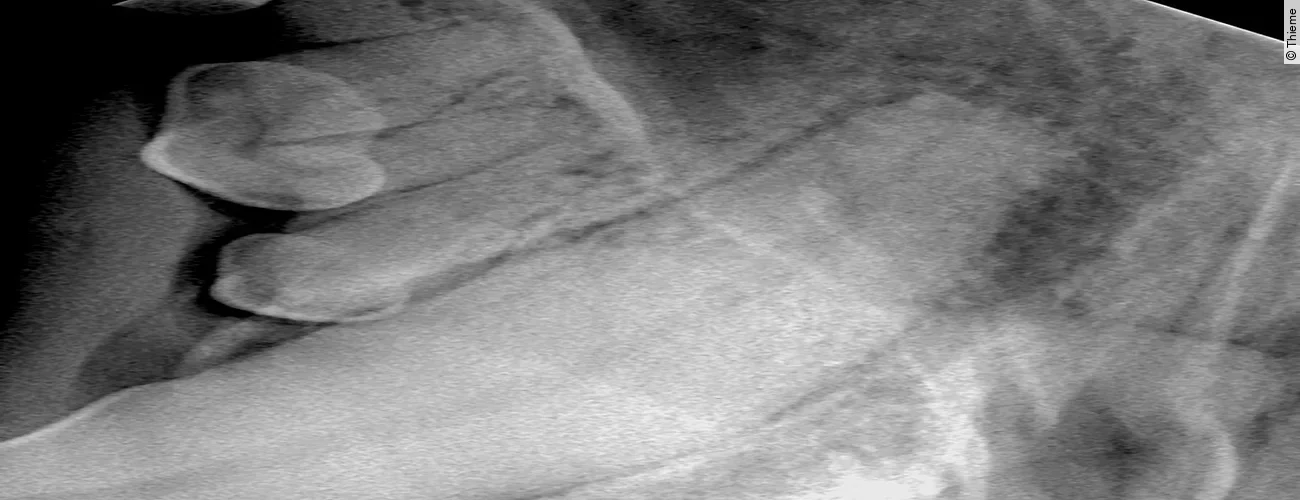

Replantation nach Avulsion Oberkieferfangzahn rechts

Der Originalartikel „Avulsion Oberkieferfangzahn rechts“ stammt aus dem Bild-Atlas der Zahnbehandlungen Hund und Katze; 2. aktualisierte Auflage; 2022.